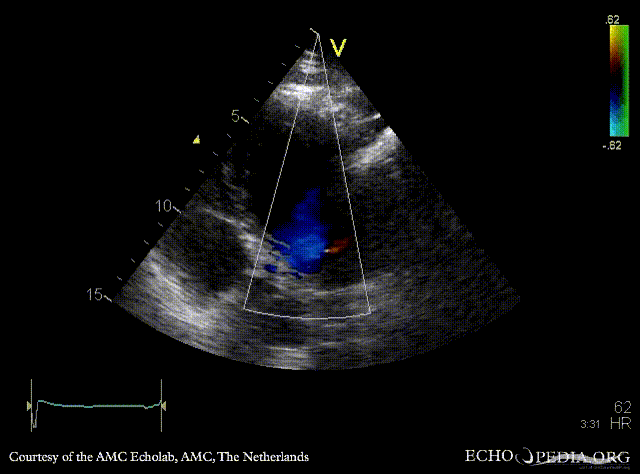

| PSAX: Color Doppler: coronary fistula | A4CH |